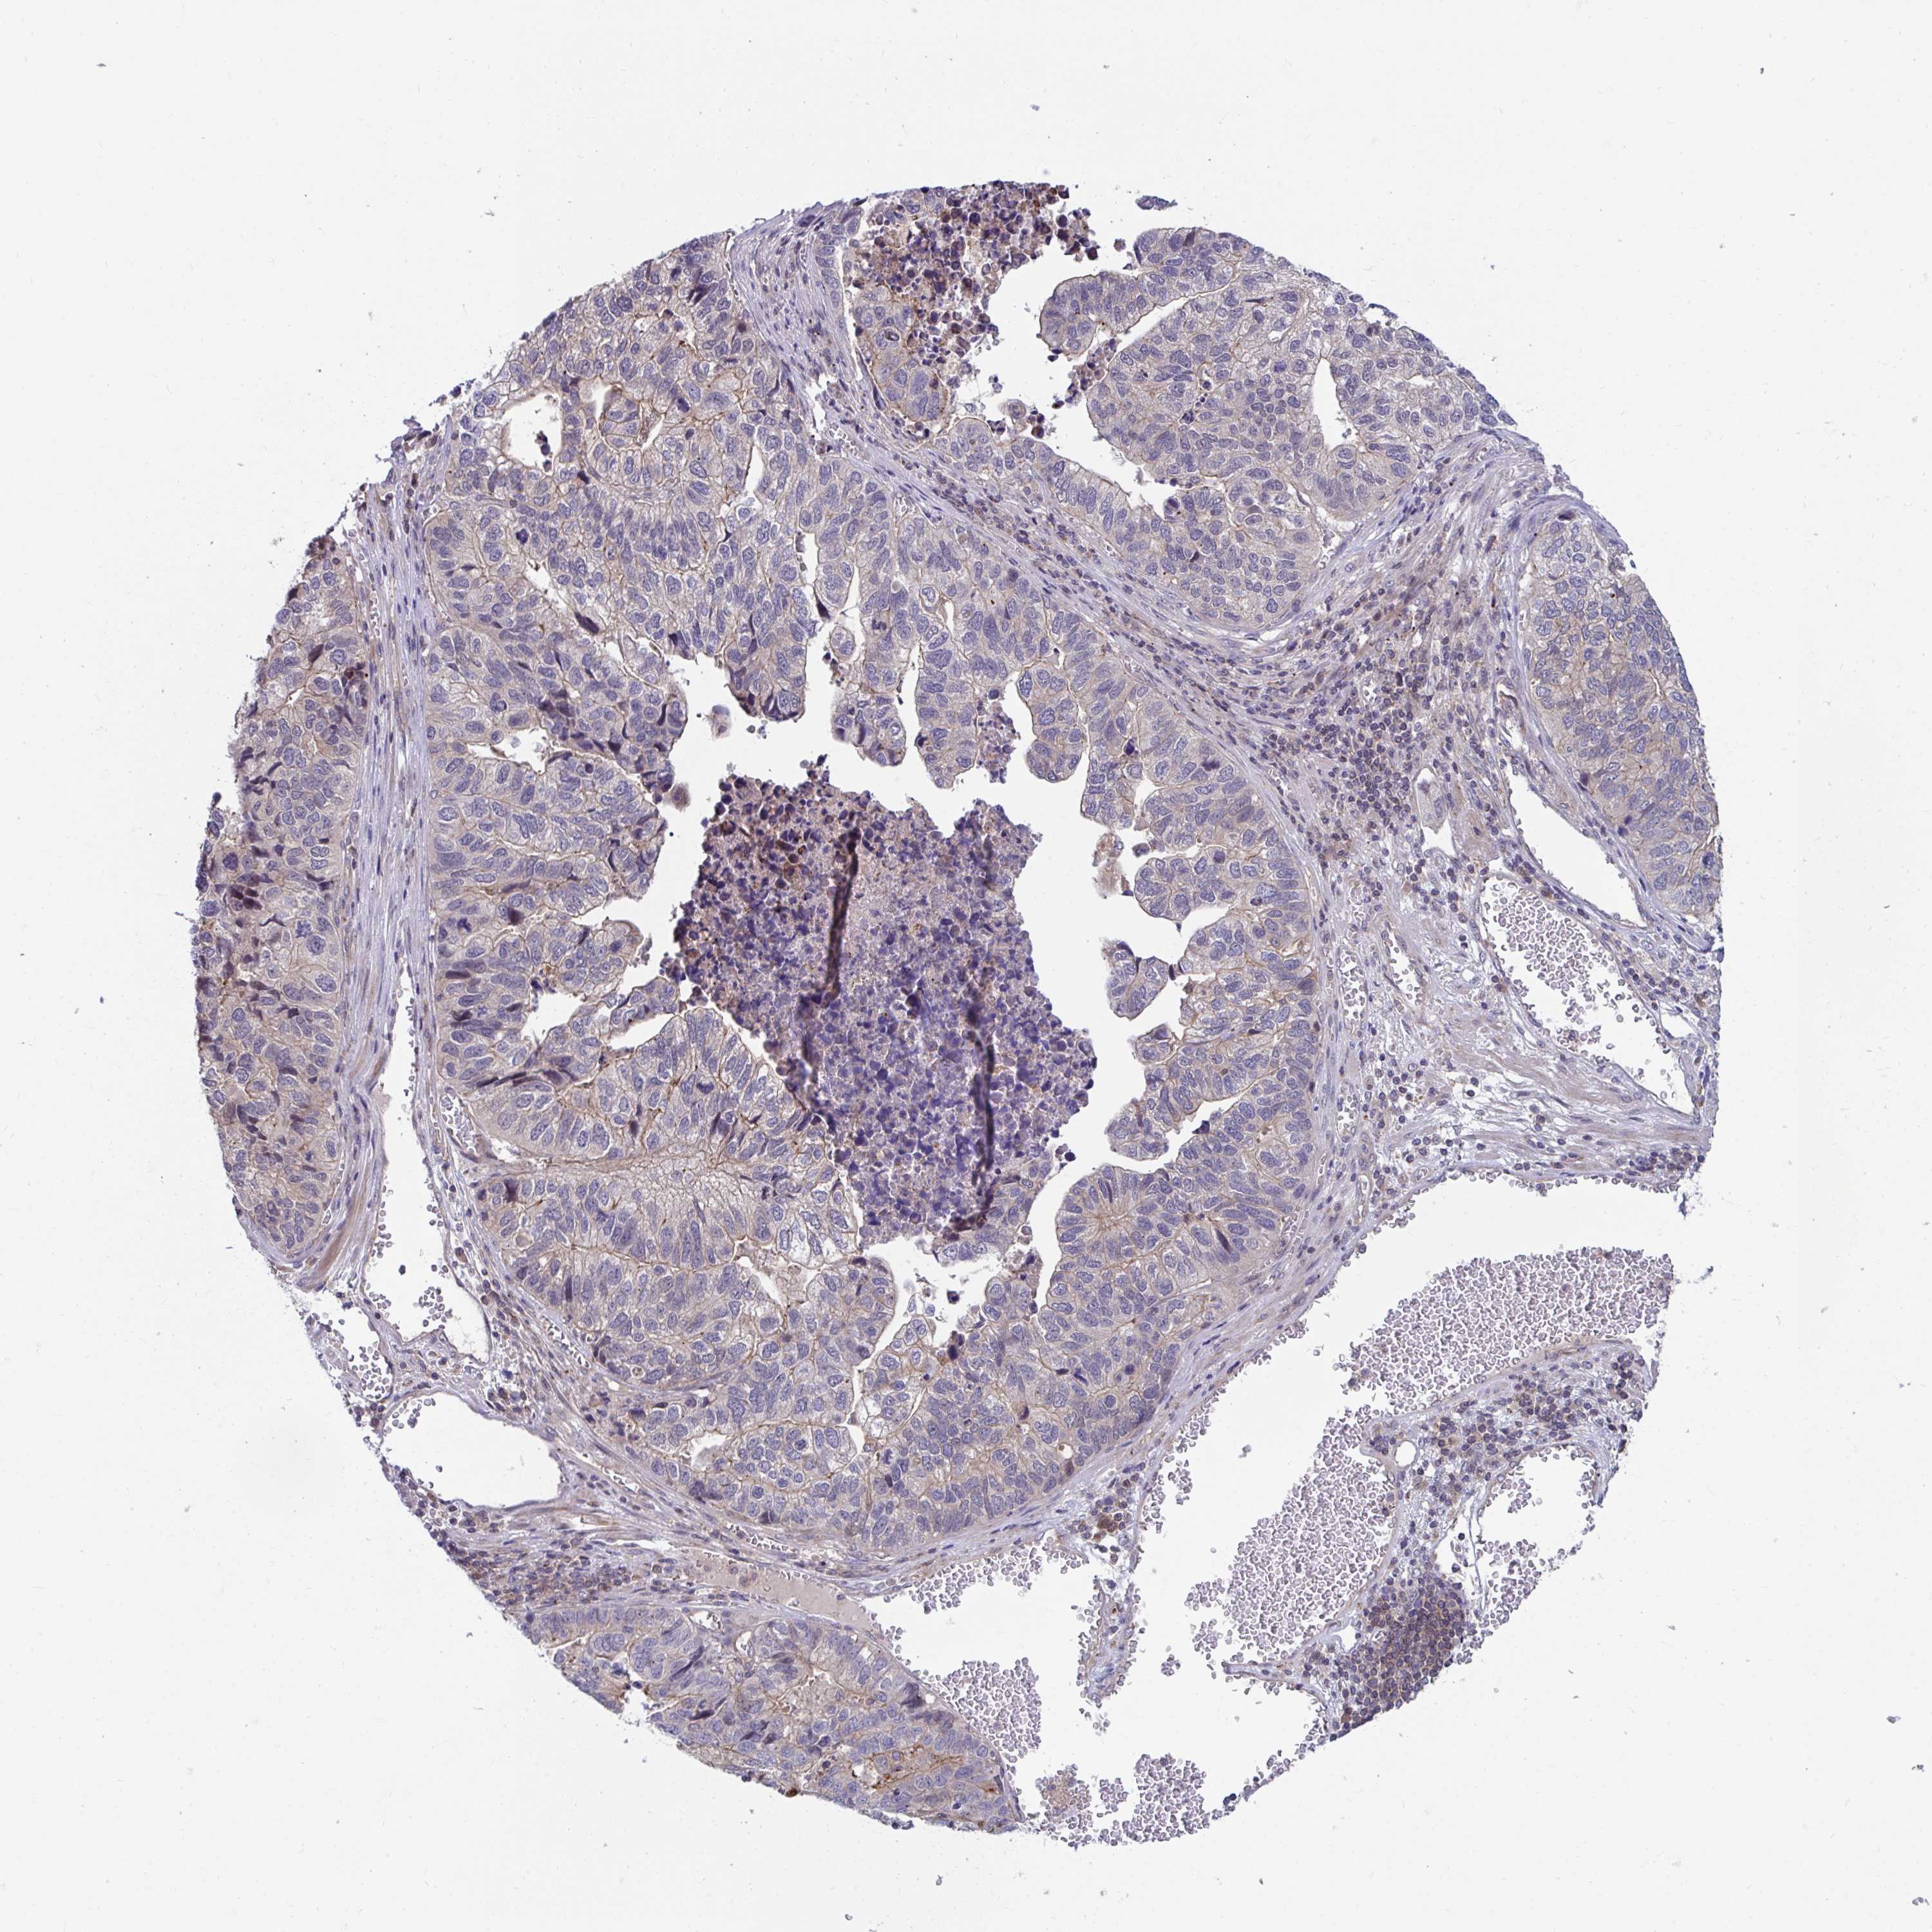

STOMACH CANCER - Protein expressioni

A mouse-over function shows sample information and annotation data. Click on an image to view it in a full screen mode. Samples can be filtered based on level of antibody staining by selecting one or several of the following categories: high, medium, low and not detected. The assay and annotation is described here.

Note that samples used for immunohistochemistry by the Human Protein Atlas do not correspond to samples in the TCGA dataset.

Antibody stainingi

Antibody staining in the annotated cell types in the current human tissue is reported as not detected, low, medium, or high, based on conventional immunohistochemistry profiling in selected tissues. This score is based on the combination of the staining intensity and fraction of stained cells.

Each image is clickable and will lead to virtual microscopy that enables deeper exploration of all samples and also displays staining intensity scores, fraction scores and subcellular localization as well as patient and tissue information for each sample.

Antibody HPA041802

Antibody HPA054532

Staining

High

Medium

Low

Not detected

Intensity

Strong

Moderate

Weak

Negative

Quantity

>75%

75%-25%

<25%

None

Location

Nuclear

Cytoplasmic/membranous

Cytoplasmic/membranous,nuclear

Adenocarcinoma, NOS

Adenocarcinoma, High grade